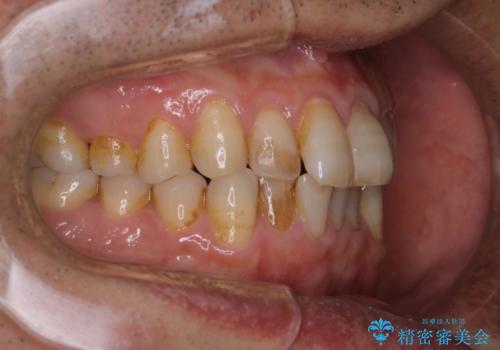

インビザラインでのマウスピース矯正中にPMTCで着色をきれいに

- インビザラインでの矯正治療中の方です。コーヒーをよく飲むため、着色が気になるとのことでした。PMTC60分コースを行いました。

PMTC(保険外治療)は、毎日の歯磨きで落としきれない汚れや、コーヒ、紅茶・タバコのヤニなどの着色も除去します。目には見えない歯と歯の間・歯肉の境目・インビザライン中はアタッチメント周囲などに残っているプラーク(歯垢)もしっかり取り除きます。PMTCでは専門的な機械や材料を使用して、徹底的に汚れを除去するため、虫歯・歯周病・口臭予防などにつながります。